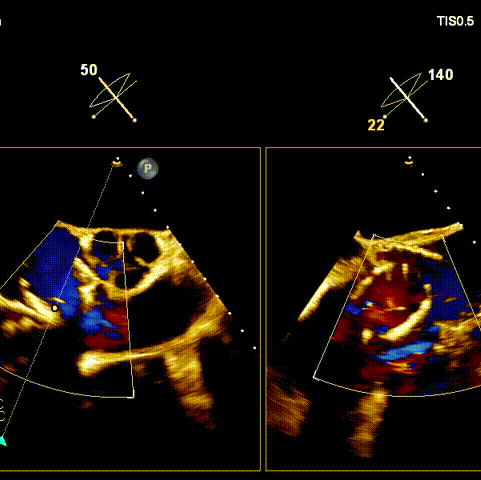

術(shù)后超聲

術(shù)前經(jīng)過(guò)全面系統(tǒng)的評(píng)估后,考慮患者存在高齡、心功能減低、三尖瓣瓣環(huán)重度擴(kuò)張(三尖瓣極重度反流)等高危因素,因此廈心結(jié)構(gòu)心團(tuán)隊(duì)聯(lián)合超聲心動(dòng)、麻醉及護(hù)理團(tuán)隊(duì),制定了詳盡的圍術(shù)期治療方案及術(shù)中治療難點(diǎn)預(yù)案。術(shù)中,由王焱院長(zhǎng)主刀,在蘇茂龍主任超聲心動(dòng)團(tuán)隊(duì)的輔助,上海市第一人民醫(yī)院陸方林主任的協(xié)助下,僅用時(shí)30分鐘,即順利完成了三尖瓣原位置換的手術(shù)。術(shù)中患者血流動(dòng)力學(xué)穩(wěn)定,術(shù)后即刻顯示LuX-Valve Plus瓣膜位置良好,固定穩(wěn)定,瓣膜功能正常,無(wú)瓣周漏。

觀摩手術(shù)的臺(tái)灣專家對(duì)此次手術(shù)過(guò)程及LuX-Valve Plus器械展示出的優(yōu)異性能表示贊譽(yù),表示與傳統(tǒng)外科三尖瓣治療方式相比,LuX-Valve Plus介入三尖瓣治療創(chuàng)傷小,安全性高,手術(shù)時(shí)間短,術(shù)中術(shù)后患者血流動(dòng)力學(xué)可平穩(wěn)過(guò)渡;且與現(xiàn)有的三尖瓣緣對(duì)緣修復(fù)手術(shù)相比,LuX-Valve Plus原位三尖瓣置換對(duì)術(shù)中影像依賴度相對(duì)更低,操作更加便捷,并且憑借獨(dú)特的錨定及瓣葉固定方式可以最大程度的避免高度房室傳導(dǎo)阻滯的發(fā)生,同時(shí)也擁有較為豐富的產(chǎn)品規(guī)格,可以適應(yīng)不同三尖瓣瓣環(huán)擴(kuò)張程度的患者,自適應(yīng)防漏環(huán)還可以有效預(yù)防瓣周漏的發(fā)生,產(chǎn)品的諸多特點(diǎn)讓與會(huì)專家再次對(duì)國(guó)產(chǎn)原創(chuàng)醫(yī)療器械刮目相看,并期望可以早日引入海峽對(duì)岸,讓臺(tái)灣地區(qū)的患者也可以使用到祖國(guó)的原創(chuàng)器械,救治更多的患者。